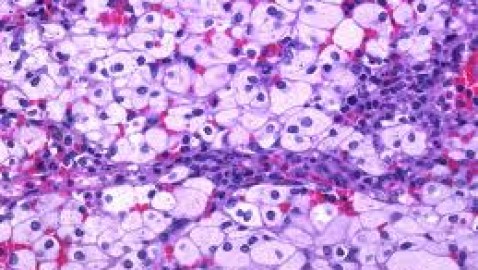

Alteraciones congénitas del catabolismo de lípidos complejos

Existe un grupo de enfermedades hereditarias caracterizadas por trastornos metabólicos resultantes en acumulación de lípidos complejos en diversos tejidos. En general, se manifiestan desde la niñez y afectan seriamente...